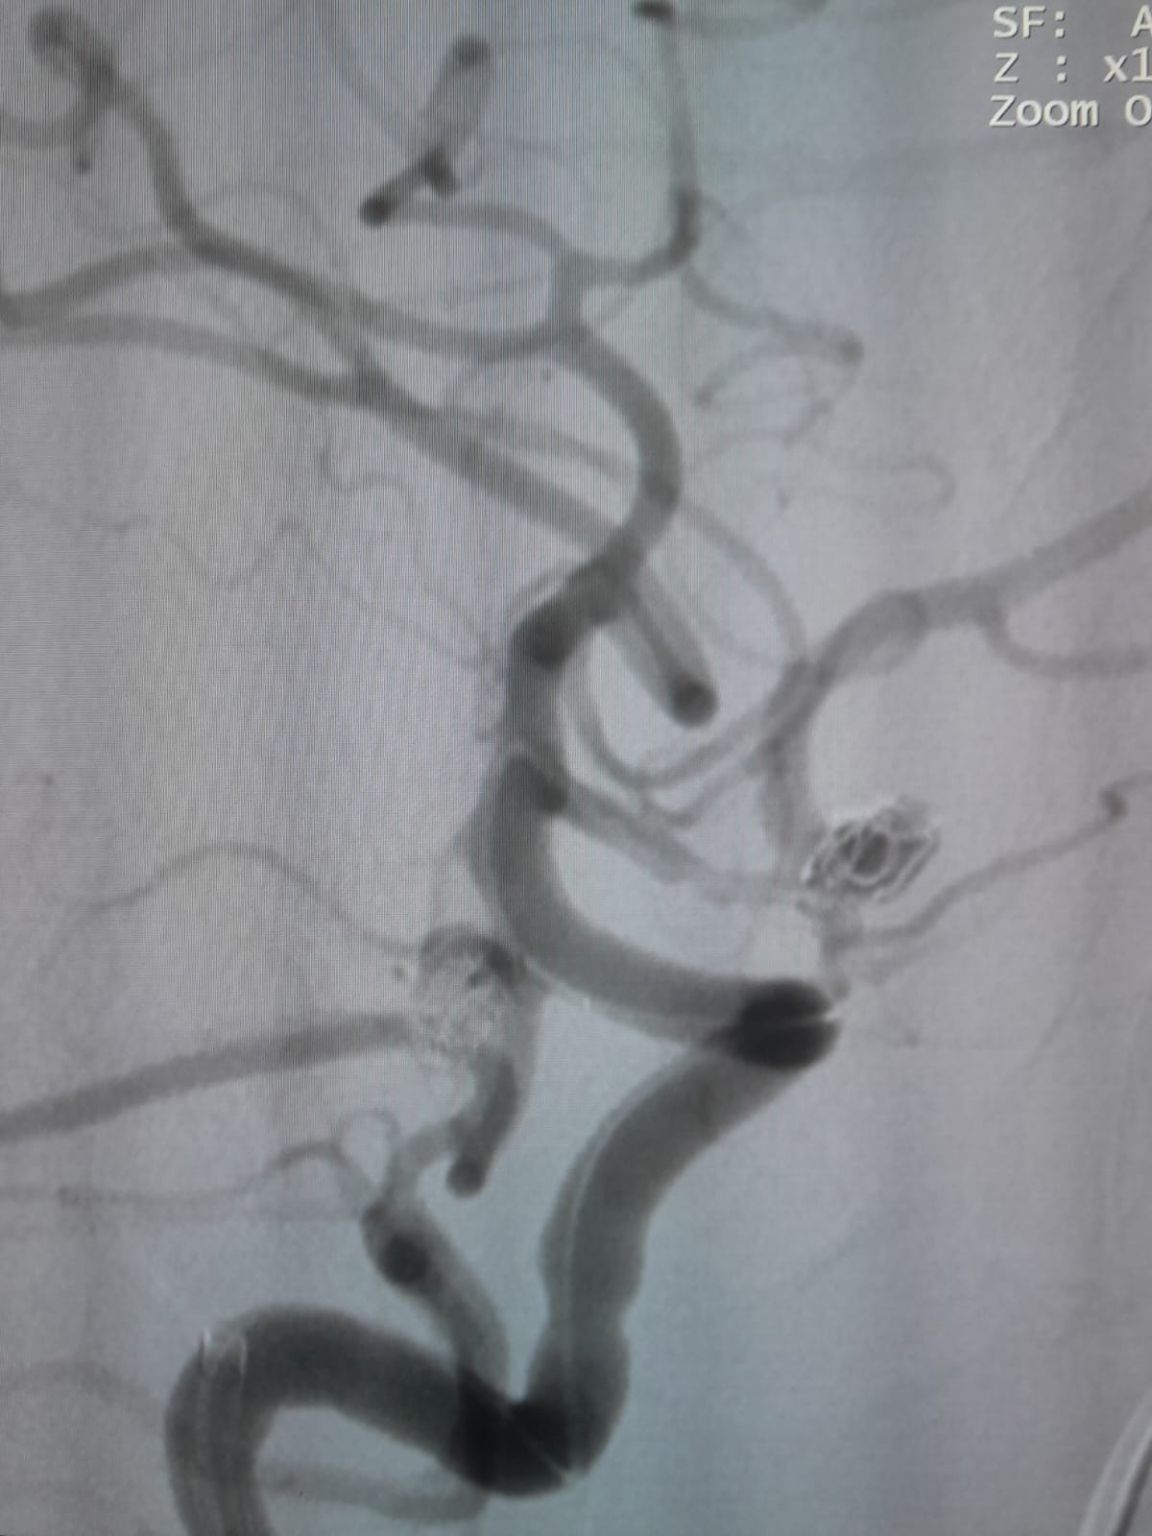

Ustanowiono dostęp naczyniowy, a następnie zespół z powodzeniem przeszedł przez Frepass®Jednorazowy mikrocewnik (TJMC14) do miejsca docelowego. Embolizację przeprowadzono przy użyciu trzech Perdenser®Embolic Coil System (TJCST4.508-3D, TJCST0306-3D, TJCST0206-3D) wdrożony wraz z Deromper®Kontroler odłączenie cewki (TJCDC).

Podczas obserwacji odnotowano wypełnienie szczątkowe w wcześniej leczonym tętniaku tętnicy łączącej tylnej. Zespół ponownie uzyskał dostęp do witryny za pomocą Frepass®Jednorazowy mikrocewnik (TJMC18 Plus) i pomyślnie wdrożył Nuva®Flow Diverter (TJED-D-4.5-16), który wykazał idealną przyłożenie do ściany i doskonałe przekierowanie przepływu, co prowadzi do bardzo zadowalających wyników leczenia.